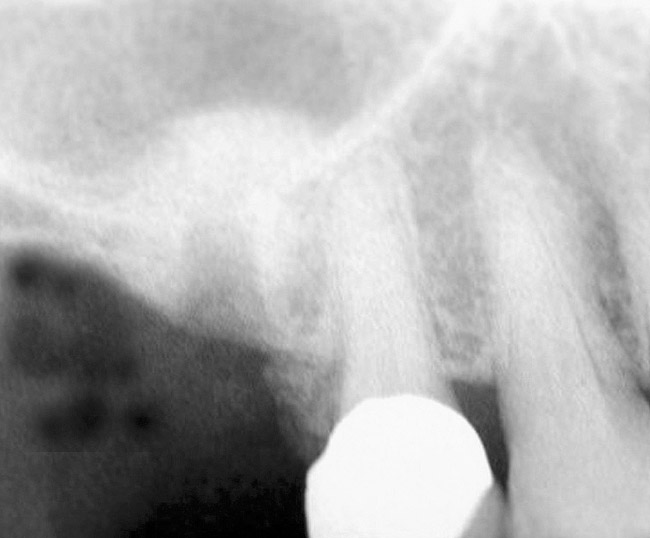

The 2-mm twist drill is used to create an osteotomy 1 mm short of the subantral floor. If any resistance is detected prior to reaching the 3-mm depth, drill penetration must be stopped, because the subantral cortical bone has possibly been reached. Any uncontrolled "push" would penetrate the bone and likely perforate the sinus membrane. A guide pin is then inserted and a radiograph taken to determine if drill penetration has terminated within 1 mm of the subantral floor (Figure 2). If the radiograph indicates that more than 1 mm of bone is present subantrally, the twist drill is used again to penetrate within 1 mm of the sinus floor. Alternately, an osteotomy tip for a piezosurgery unit can be used for this purpose. The final depth of penetration should be verified with another periapical film.

Figure 2  After drilling to a depth of 3 mm with a 2.1-mm twist drill, the guide pin was placed and a radiograph was taken to ascertain if the drill stopped within 1 mm of the subantral floor.

Figure 2

Figure 9: After the extraction, a 2.1-mm twist drill was used to drill within 1 mm of the subantral floor. A guide pin was placed and a radiograph was taken to ascertain if the drill stopped within 1 mm of the subantral floor.

Figure 9